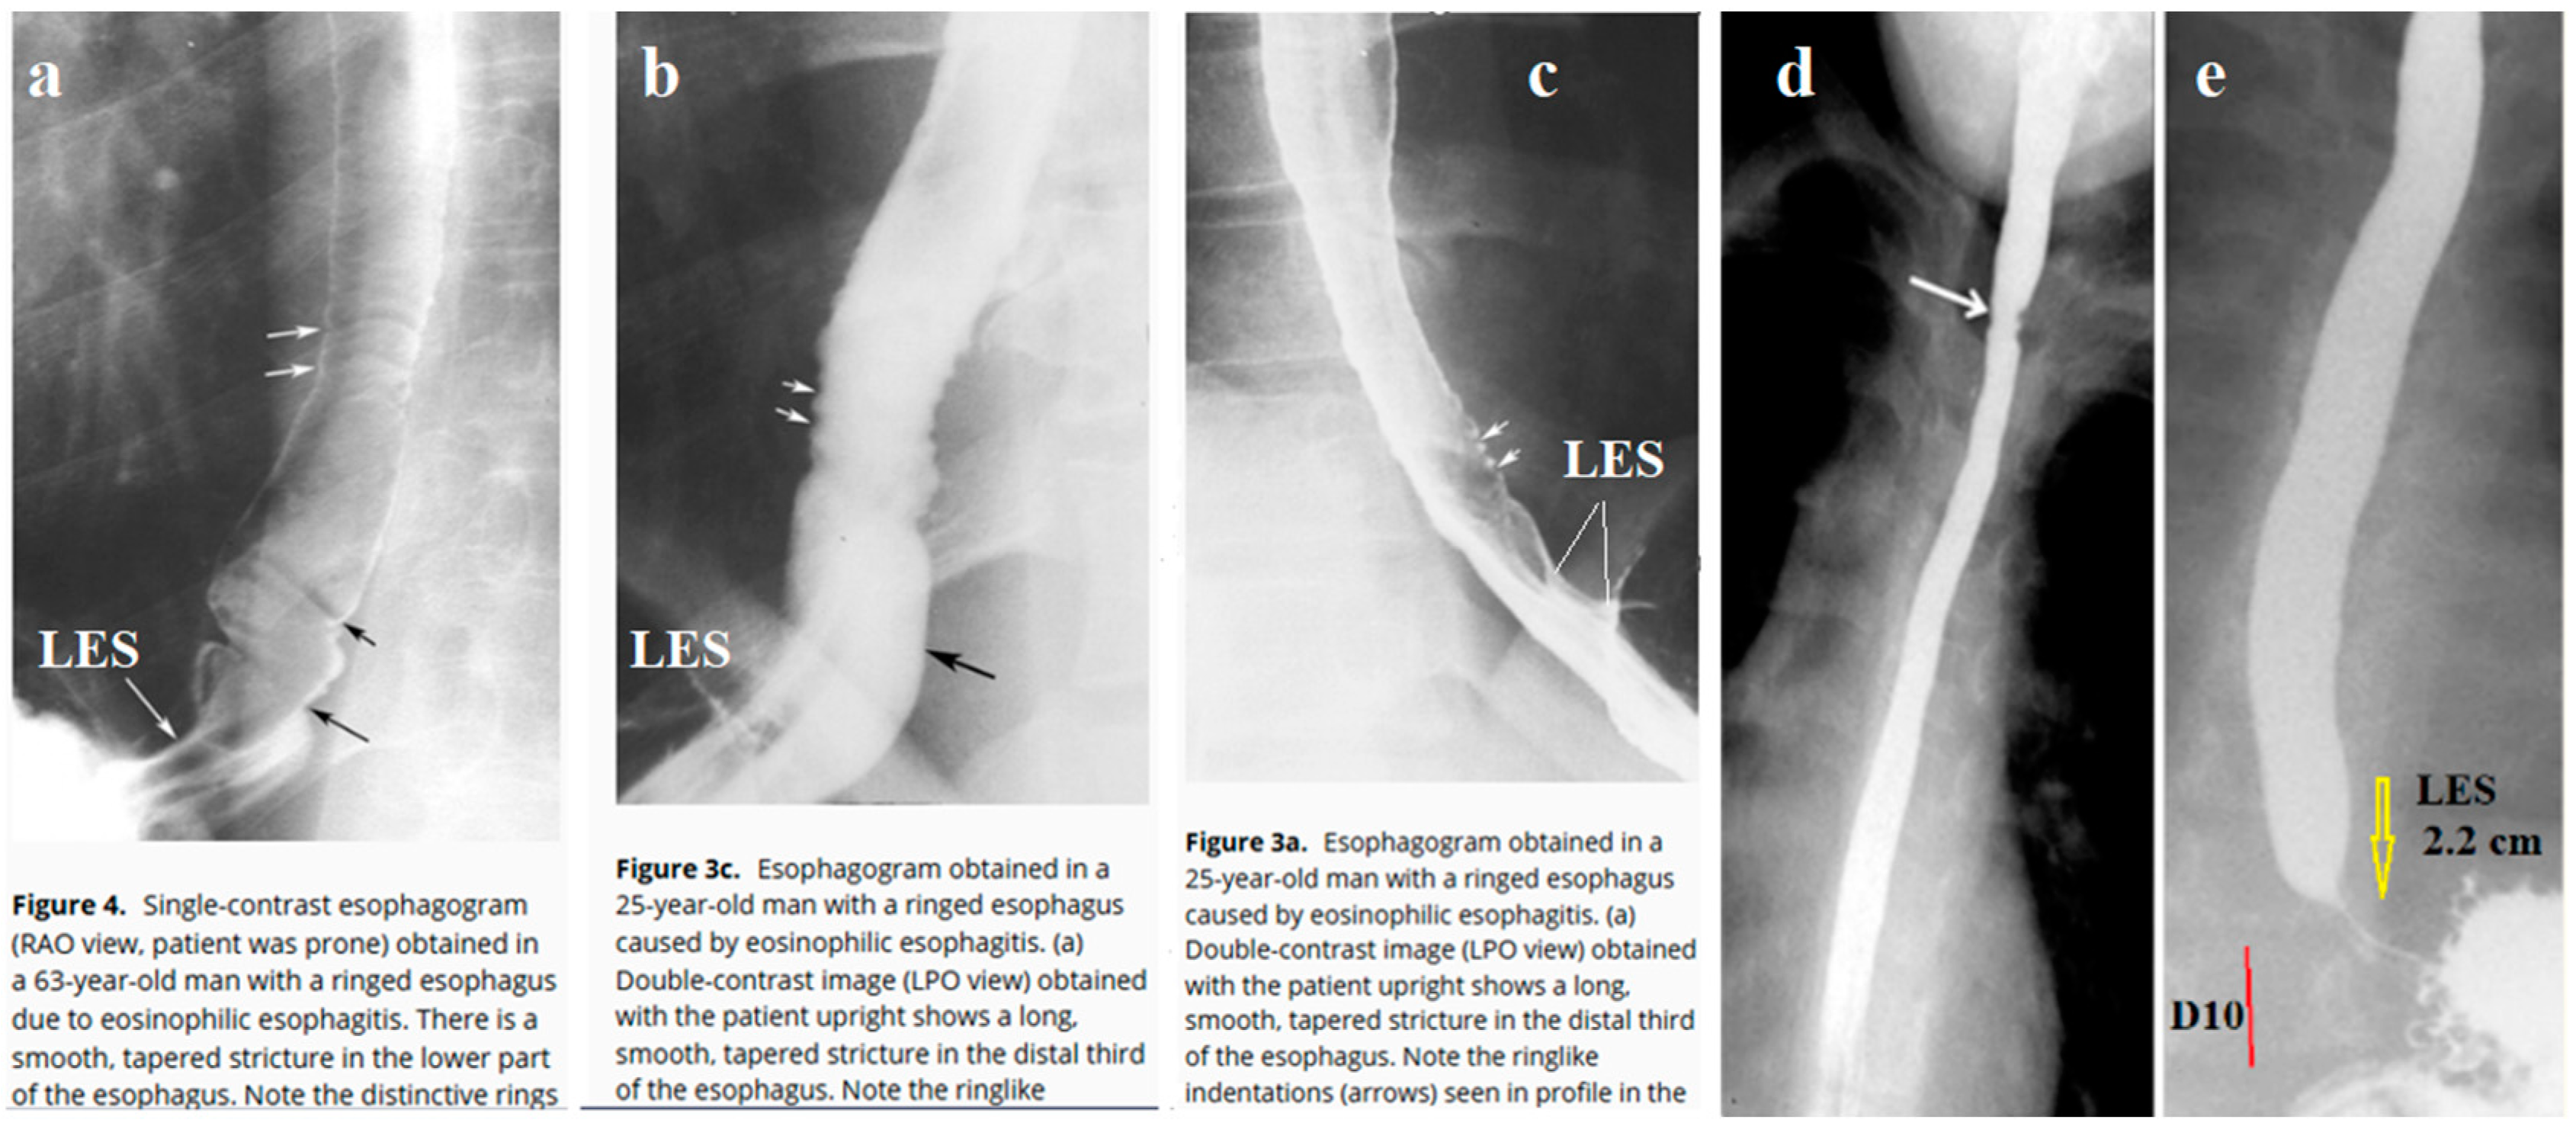

6. In the available literature, I found 10 cases of radiographic examination in patients with EoE, where the radiograph, in addition to the esophagus, captured the esophagogastric junction. All authors drew attention to the narrow width of the esophagus and the presence of erosions. Meanwhile, in all cases, I discovered the pathological function of the lower esophageal sphincter (LES). Figure 1 shows the most demonstrative radiographs.

Barium swallow study is frequently normal in pediatric EoE except for narrow-caliber esophagus [39]. In adults at barium studies in seven patients (50%), the strictures contained multiple fixed ringlike indentations that produced a ringed esophagus. The ringlike indentations appeared as multiple, fixed, closely spaced, concentric rings traversing the stricture. Ten (77%) had hiatal hernias and nine (69%) had reflux during X-ray examination [38]. The analysis of radiographs found in published articles confirms the hypothesis that EoE is in most cases accompanied by reflux of barium into the esophagus. This is evidenced by both the detection of the episodes of reflux and the shortening of the dilated and sometimes gaping LES.

Thus, radiological studies confirm the role of reflux in the pathogenesis of EoE.

Figure 1. Radiographs of patients with EoE. (a-b-c) from the article by Zimmerman et al [38] with parts from figure captions. (a) In a 68-year-old patient, I have shown a short, wide, and folded LES. (b) In a 25-year-old patient, a wide, gaping LES is visible. (c) In the same patient, in another projection, it is visible that the LES is significantly shorter than normal. (d-e). From the article by Al-Hussaini et al [39]. (d) Barium esophagogram in a 15-year-old patient shows a stricture at 3 cm below upper esophageal sphincter, long-segment narrow caliber in middle and lower esophagus. (e) In the same patient after three sessions of the esophageal dilation (up to size 14 mm) I show a shortened LES to 2.2 cm in length, which is significantly shorter than the age norm (≈3.6 cm).